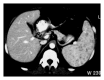

Non-Hodgkin and Hodgkin lymphomas frequently involve many structures in the abdomen and pelvis. Extranodal disease is more common with Non-Hodgkin's lymphoma than with Hodgkin's lymphoma. Though it may be part of a systemic lymphoma, single onset of nodal lymphoma is not rare. Extranodal lymphoma has been described in virtually every organ and tissue. In decreasing order of frequency, the spleen, liver, gastrointestinal tract, pancreas, abdominal wall, genitourinary tract, adrenal, peritoneal cavity, and biliary tract are involved. The purpose of this review is to discuss and illustrate the spectrum of appearances of nodal and extranodal lymphomas, including AIDS-related lymphomas, in the abdominopelvic region using a multimodality approach, especially cross-sectional imaging techniques. The most common radiologic patterns of involvement are illustrated. Familiarity with the imaging manifestations that are diagnostically specific for lymphoma is important because imaging plays an important role in the noninvasive management of disease.